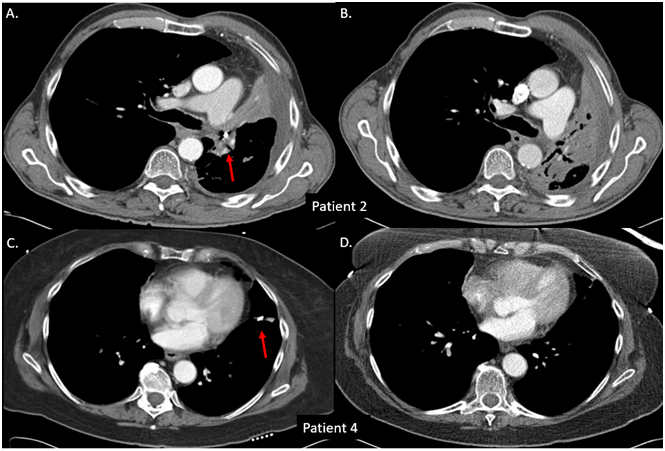

Figure 3 Coils lost after radiotherapy. Patient 2-left hilar fiducial-A. Initial placement and B. 10-month follow-up. The marker was last seen at an 8-month follow-up. Patient 4-left intrapulmonary fiducial-C. Initial placement and D. 4-month follow-up. The marker was last seen at a 2-month follow-up.